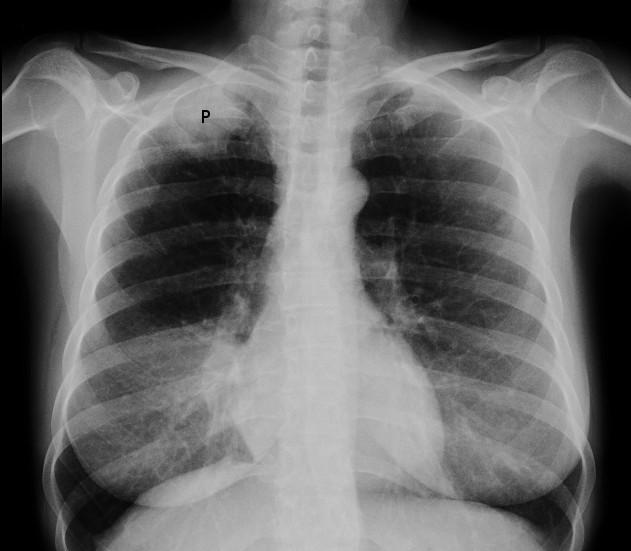

X-ray image of Pancoast tumour

© Jmarchn (Own work), CC BY-SA 3.0, via Wikimedia Commons

By Jmarchn, CC BY-SA 3.0, via Wikimedia Commons